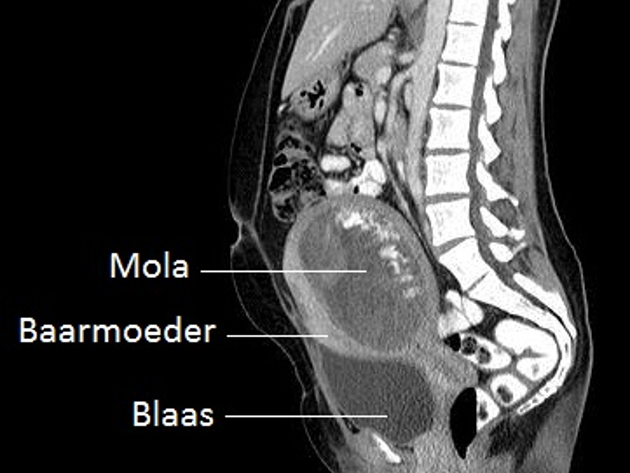

Hiernaast ziet u een voorbeeld van een CT-scan die een mola-zwangerschap laat zien.

De afkorting CT staat voor 'Computer Tomogram'. De CT-scanner werkt met dezelfde röntgenstralen als bij een 'gewone' röntgenfoto.Alleen maakt de CT-scanner dwarsdoorsneden van het lichaam, waardoor de arts als het ware plakjes van het lichaam kan zien. Als alle gefotografeerde plakjes achter elkaar worden gelegd, ontstaat een driedimensionaal beeld.